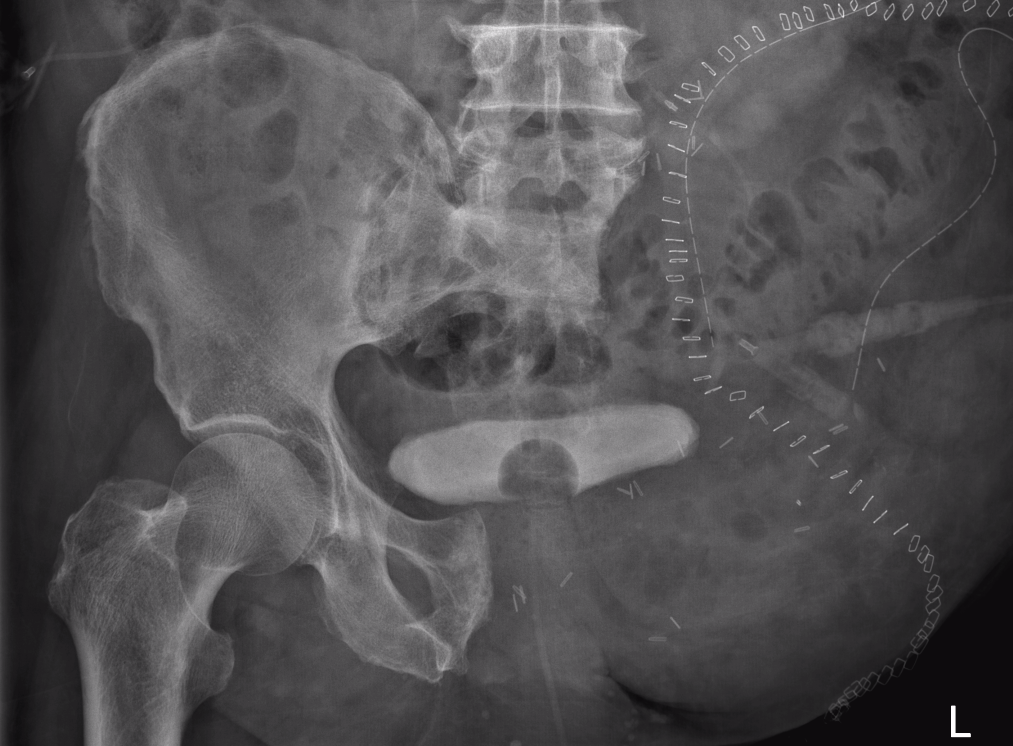

Location

Axial skeleton 31%

- 20% pelvis

X-ray

Lytic lesion with punctate or spotty calcification

Worrisome features

- growth over time

- large > 5cm

- endosteal scalloping is hallmark of chondrosarcoma